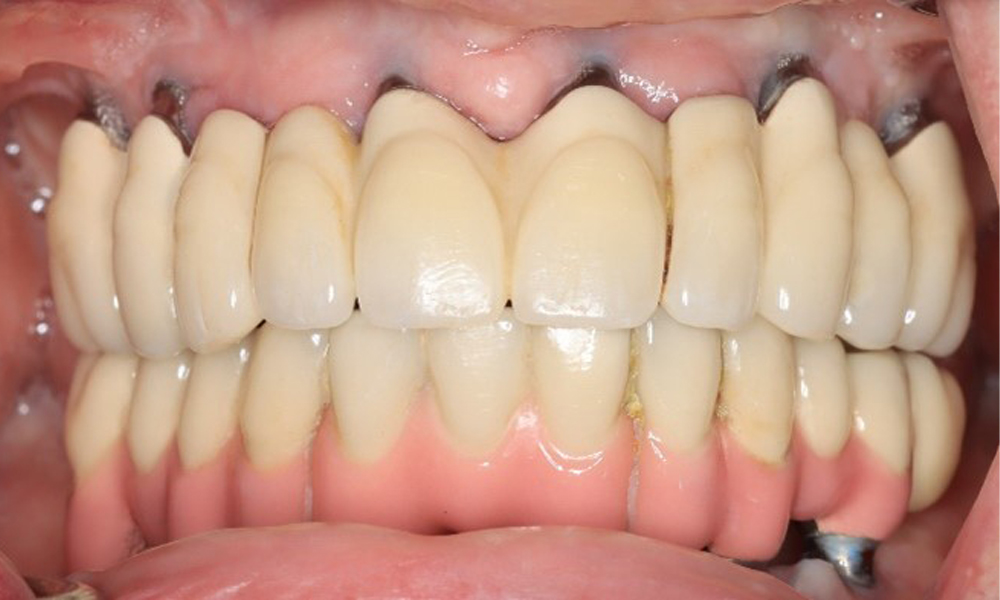

74-годишен пациент се явява за консултация. Анамнезата показва, че пациентът има добре контролирана хипертония и приема Lixiana. Освен това пациентът е имал карцином на бъбрека през 2020 г. Начинът на живот на пациента е без забележки. Няма останали естествени зъби и има шест импланта в горната и долната челюст, на които са поставени коронки или мостове. Текущите данни не показват периимплантатен мукозит или периимплантит, но въпреки това периодично има (незначително) кръвене при имплантите (възстановяванията).

Възстановявания: импланти в области 011, 013, 015, 021, 023, 025, 031, 033, 035, 042, 044, 046

Понастоящем състоянието на периимплантатите е стабилно. Поради сложността на надстройките пациентът има умерен риск от развитие и нисък риск от прогресия на периимплантни заболявания.